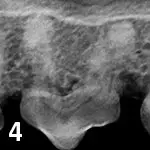

A radiographic image showing the dental structure of a canine, highlighting the roots and surrounding bone. The image reveals potential periodontal disease with visible bone loss around the teeth.

Figure 4

Maxillary third premolar affected by external replacement resorption.

External replacement resorption (See Figure 4) appears as decreased periodontal ligament space with partial replacement of root tissues by the surrounding alveolar bone. It is associated with injuries that lead to necrosis of the periodontal ligament fibers and is thought to be progressive.